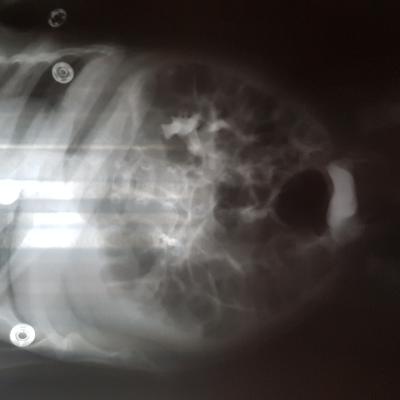

Добрый день! Еще внутриутробно у ребенка обнаружили расширение лоханок.Провели обследование в 1.5 месяца.Поставили диагноз болезнь Ормонда.И назначили консервативное лечение.В 2ух мочеточниках по несколько наростов.рефлюкса не было.Скажиье, возмлжнл что ребенок поосто перерастет?

Болезнь Ормонда (ретроперитонеальный фиброз, забрюшинный фиброз) – хроническое воспаление жировой клетчатки забрюшинного пространства, которое постепенно приводит к компрессии и нарушению проходимости трубчатых структур данного анатомического участка. Чаще всего, в качестве этих тубулярных структур выступают мочеточники.

У меня есть сомнения, что причиной гидронефроза в Вашем случае явилось именно это состояние.